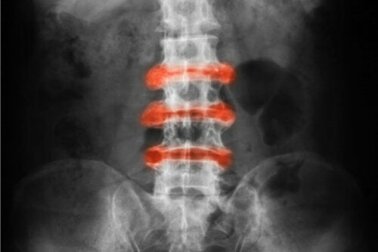

La spondilite anchilosante viene descritta come una forma di artrite infiammatoria localizzata soprattutto a carico delle articolazioni di schiena e pube.

- Anchilosante: forma di artrite infiammatoria con particolare incidenza sulla colonna vertebrale.